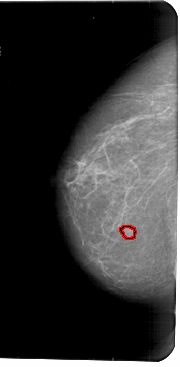

A_1776_1.LEFT_CC

LEFT_CC LINES 5491 PIXELS_PER_LINE 2686 BITS_PER_PIXEL 12 RESOLUTION 43.5 OVERLAY

FILE: A_1776_1.LEFT_CC.OVERLAY

TOTAL_ABNORMALITIES 1

ABNORMALITY 1

LESION_TYPE MASS SHAPE IRREGULAR MARGINS ILL_DEFINED

ASSESSMENT 4

SUBTLETY 3

PATHOLOGY BENIGN

TOTAL_OUTLINES 1

BOUNDARY